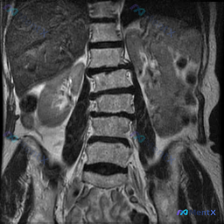

整理到一份腰椎MRI T2冠状位的影像资料,很有意思。 第一眼扫过去,视觉上似乎有点「脊柱侧弯」的感觉,但仔细看影像描述和序列本身——腰椎生理力线其实基本是正的,椎体序列也规整,没有明显的结构性侧弯。 真正跳出来的异常完全在别的地方: - 椎间盘有脱水变性,椎体边缘有骨赘(轻中度退变,这个不是重点)...

整理到一份腹部MRI的影像分析资料,有点意思——用户最初的疑问是“这张图能看到脊柱侧弯吗”,但读下来发现,真正可能需要紧急处理的问题不在脊柱,而在脾脏。 先不说结论,先放关键影像表现: 1. 肝脏、胆道、胰腺、双肾(除右肾位置稍低)未见明显重大异常; 2. 脾脏明显增大,下极到腰椎中下段,实质内弥漫...